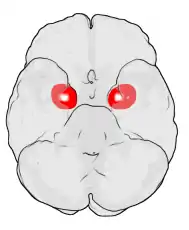

Location of the amygdalae in the human brain

The amygdala (/əˈmɪɡdələ/; pl.: amygdalae /əˈmɪɡdəli, -l/ or amygdalas; also corpus amygdaloideum; Latin from Greek, ἀμυγδαλή, amygdalē, 'almond', 'tonsil'[1]) is a paired nuclear complex present in the cerebral hemispheres of vertebrates. It is considered part of the limbic system.[2] In primates, it is located medially within the temporal lobes.[3] It consists of many nuclei, each made up of further subnuclei. The subdivision most commonly made is into the basolateral, central, cortical, and medial nuclei together with the intercalated cell clusters.[4] The amygdala has a primary role in the processing of memory, decision-making, and emotional responses (including fear, anxiety, and aggression). The amygdala was first identified and named by Karl Friedrich Burdach in 1822.[5]